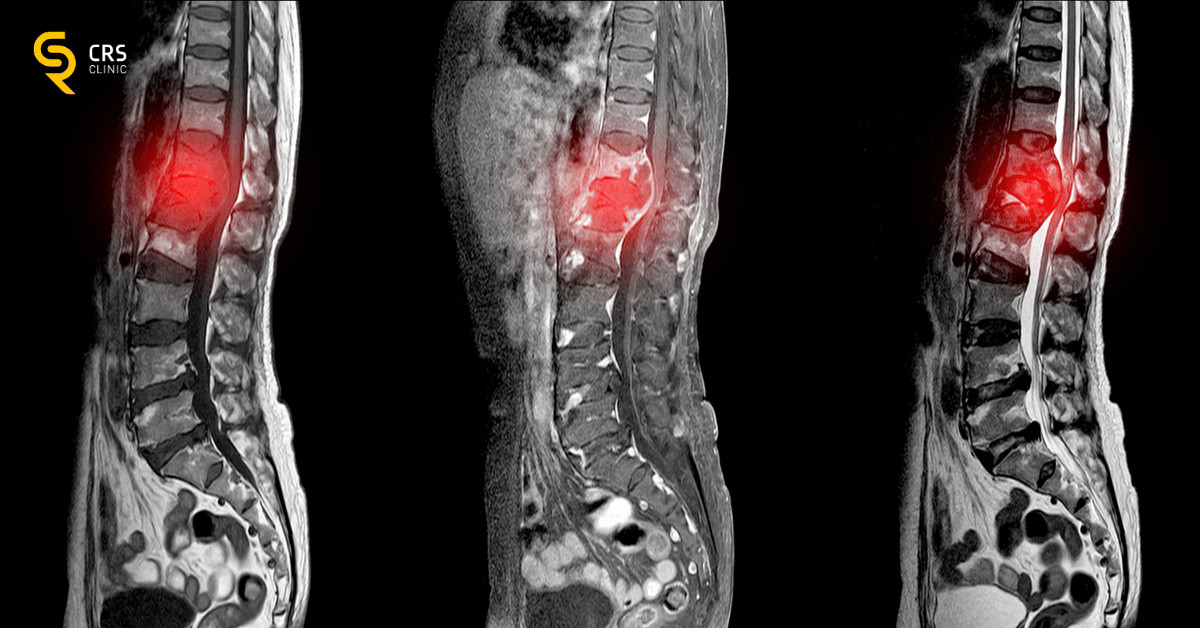

Najdokładniejszą metodą obrazowania jest rezonans magnetyczny kręgosłupa, który pozwala na ocenę struktury krążków międzykręgowych, rdzenia kręgowego, kanału kręgowego oraz korzeni nerwowych. W niektórych przypadkach pomocna może być także tomografia komputerowa.

Dyskopatia to poważne schorzenie, które może znacząco ograniczyć komfort życia, szczególnie gdy obejmuje odcinek lędźwiowy i prowadzi do rozwoju rwy kulszowej. Jej przyczyny i objawy są różnorodne – od przeciążeń i urazów, po siedzący tryb życia i wady postawy. Kluczem do skutecznego leczenia jest szybka diagnostyka dyskopatii, w tym wykonanie rezonansu magnetycznego, oraz indywidualnie dobrane leczenie dyskopatii – zachowawcze lub chirurgiczne.